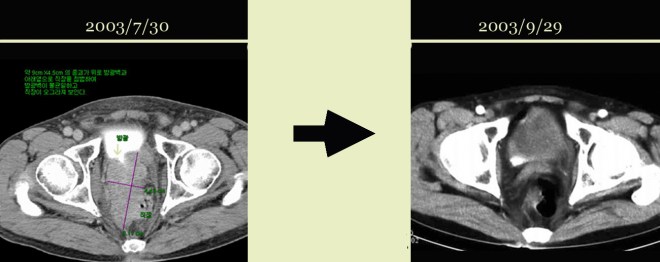

전립선암이 열어 보니 방광 대장을 다 침범하여서 거의 9cm 이상의 종양이 퍼져 있었고, 주변 ischial lymph node(골반 주위의 림프절)의 다발성전이가 있었던 분이다. 이후 본원에 와서 양방에서는 사용치 않는 양성 전립선비대를 억제하는 프로스카와 본원의 한방요법을 결합하여 전립선암이 거의 없어진 상태로  3년 이상을 정상생활을 하였고 그 후 술 담배를 다시 하기 시작하고 일년만에 다발성 폐전이가 되어서 폐렴합병증으로 사망한 사례이다. 자료를  2000 년도의 자료라 찾기가 어려워서 나중에 더 보충 자료를 넣어 보려고 하지만 본고에서는  2007 년도 본인이 삼성의료원의 산부인과 배덕수 과장 소개로 한의학의 암치료에 대한 강의를 초청받아서 갔을 때 자료를 가지고 이 환자의 사례를 설명해 보겠다.

1-2.JPG

나이는 74세로 당시 뼈전이와 골반벽전이 대장방광전이가 있어서 열었다 바로 닫아버리고  2달선고를 받고 나서 한방을 찾았다. 위에서 보듯이 경추에 전이가 있었고, 아래 사진과 같이 약 9cm 정도의 종양이 방광벽을 침범하여서 방광이 일그러져 보이고(하얀 소변이 찬 부분 아래쪽면) 대장도 밀려서 화살표에서 보는 작은 점이 남아 있는 대장의 크기로 대변을 거의 못 보다시피 가늘게 나왔다.

1-6.jpg

이 환자는 두 달여의 치료에 좌측 사진에서 보듯이 왼쪽 골반벽의 종양이 모두 소실이 되어서 아래 사진에서 보이지 않고, 우측도 마찬가지로 이전 검은 화살표에서 보는 방광벽의 침범이 아래 사진에서는 정상 소변이 차서(조영제가 하얗게 보임) 면이 매끄럽게 다 없어지고, 아래 대장쪽도 다 소실이 된 상태이다.